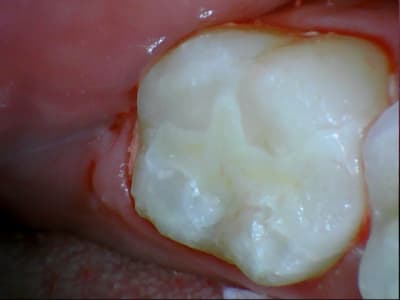

31/10/2011 à 18h09

tiens je me suis chronométré :)

28min :) lol

bon celui la etait un peu long, car provisoire collé au cvi cause durée avec le provisoire trop longue....

donc dur a déposer et obligé d'enlever les résidu de cvi aux US...

ceux qui font pas d'onlay vous proposez quoi là ?

patiente de 13 ans ...

Ca ressemble à un beau MIH avec un confrère qui a fait des trucs bizarres avec un amalgame.

Oui MIH déjà avec une belle récidive de carie. Je pense que dans un cas comme ça le compo est voué très vite à l’Échec...